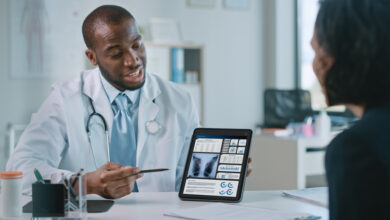

Estos son los exámenes que permiten detectar el cáncer de pulmón

El cáncer de pulmón es considerado la primera causa de muerte entre los diferentes tipos de cáncer que existen en…

Leer más » -